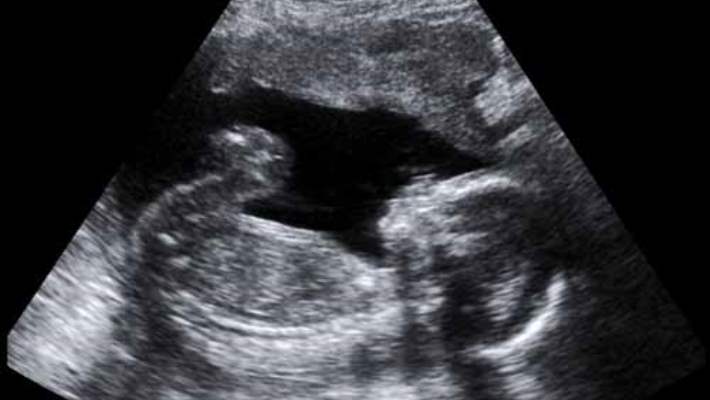

Fetal ultrason veya sonogram, rahimdeki bir bebeğin görüntülerini oluşturmak için yüksek frekanslı ses dalgaları kullanan bir görüntüleme tekniğidir. Fetal ultrason görüntüleri, doktorunuzun bebeğin gelişimini değerlendirmesini ve gebeliğin nasıl ilerlediğini gözlemlemesini sağlar. Fetal ultrason aynı zamanda, doğumdan aylarca önce bebeğinizin profilini inceleme ve onun ufak kalp atışlarını izleme olanağı verir. Bazı durumlarda fetal ultrason, muhtemel sorunları değerlendirmek veya bir teşhisi doğrulamak için de kullanılır.

Fetal ultrason çoğunlukla, hamileliği doğrulamak ve zamanını belirlemek için birinci trimester (üç aylık) dönemde ve anatomik detayların daha da görünebilir olduğu ikinci trimester (18 ve 20’nci haftalar arası) dönemde yapılır. Eğer bebeğinizin sağlığının daha yakından gözlemlenmesi gerekiyorsa, ultrason hamilelik boyunca tekrarlanabilir.

Doktorunuz veya teknisyen trandüseri karnınız üzerinde ileri geri götürecektir. Kemiklerinizden ve diğer dokularınızdan yansıyan ses dalgaları bir ekran üzerinde siyah beyaz veya gri görüntülere dönüştürülür. Doktorunuz veya teknisyen bebeğinizin başını, karnını, kalça kemiğini ve diğer yapıları ölçer. Önemli yapıları belgelemek için belli görüntüler yazdırılacak veya depolanacaktır. Size görüntülerden bazılarının kopyalarının verilmesi muhtemeldir.

Bebeğinizin pozisyonuna ve gelişim aşamasına bağlı olarak yüzünü, ellerini ve parmaklarını veya kolla bacaklarını ayırt edebilirsiniz. Eğer bebeğinizi “göremezseniz” endişe etmeyin. Ultrason görüntülerini eğitimli olmayan bir gözlemcinin deşifre etmesi zordur. Doktorunuzdan veya teknisyenden ekranda görünenleri açıklamasını isteyin.